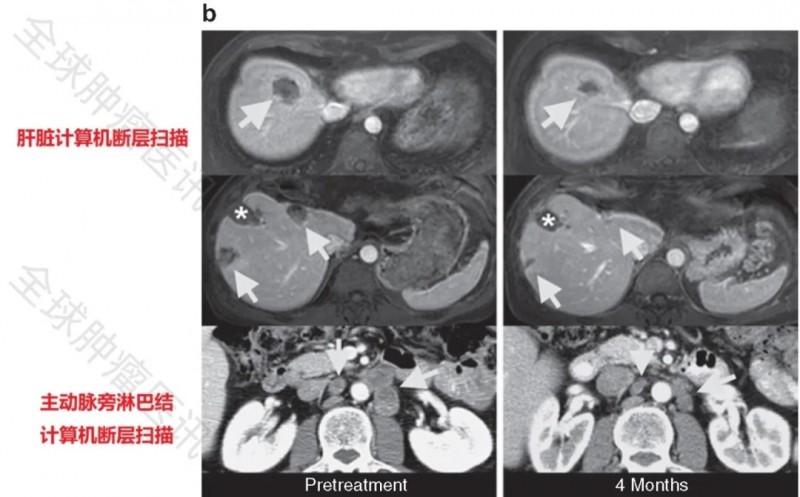

患者3在治疗后3个月的随访中,肝脏、肺部及主动脉旁淋巴结转移灶缩小34%,至治疗后4个月时肿瘤进一步缩小49%(图1b),符合RECIST标准定义的确认部分缓解(PR)。下图展示了患者3在治疗前、治疗后4个月的计算机断层扫描图像:箭头所示为结直肠癌转移灶位置,星号标记为此前经射频消融(RFA)治疗的肝转移部位所形成的肝脏缺损。

▲图源“Molecular Therapy”,版权归原作者所有,如无意中侵犯了知识产权,请联系我们删除